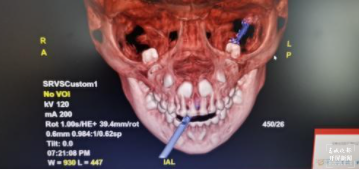

医生对孩子进行初步检查后发现,孩子神志清醒,各项生命体征平稳。为了查清楚木棍插入的深度和具体位置,医生对孩子的头部进行了CT扫描 ,结果显示,这根棍子自孩子左侧口腔内戳入,直插颈部,位于颈动脉三角内。(颈动脉三角:颈动脉位于颈部,因其内含有颈内静脉及其属支、颈总动脉及其分支而得名,除血管外还有舌下神经,副神经等神经从这里穿行)。

贸然拔出竹签,会导致孩子大失血,造成失血性休克,死亡风险极高。为了给手术医师更好地评估手术风险,CT室值班医师给患儿进行了三维重建,长约15cm左右的棍子插进体内约7cm,直达患儿颈后,从患儿颈背部可以用手触及竹签顶端。